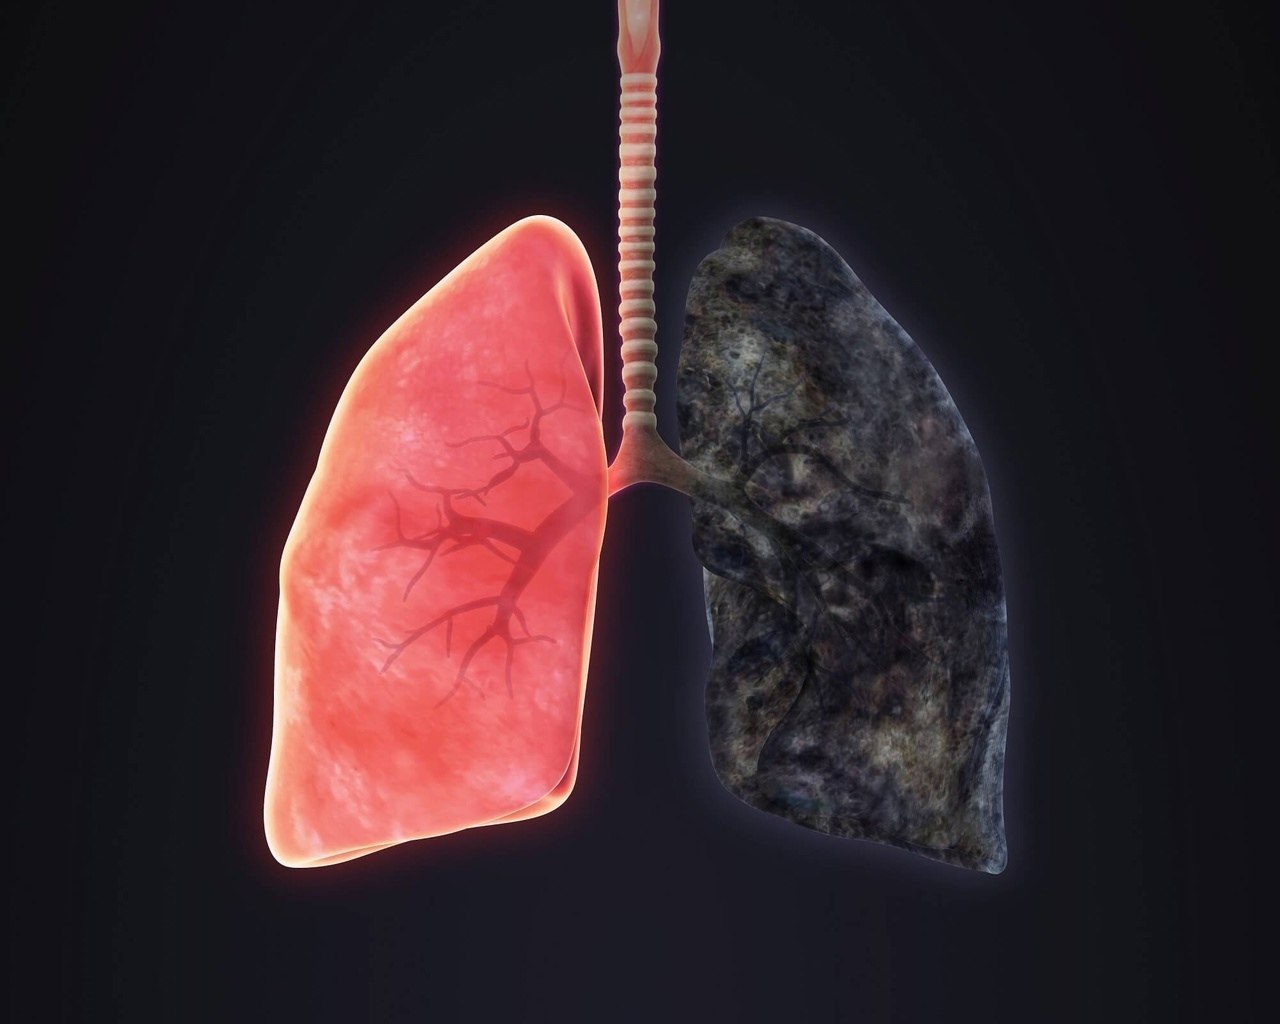

Здоровый образ жизни: Влияние курения